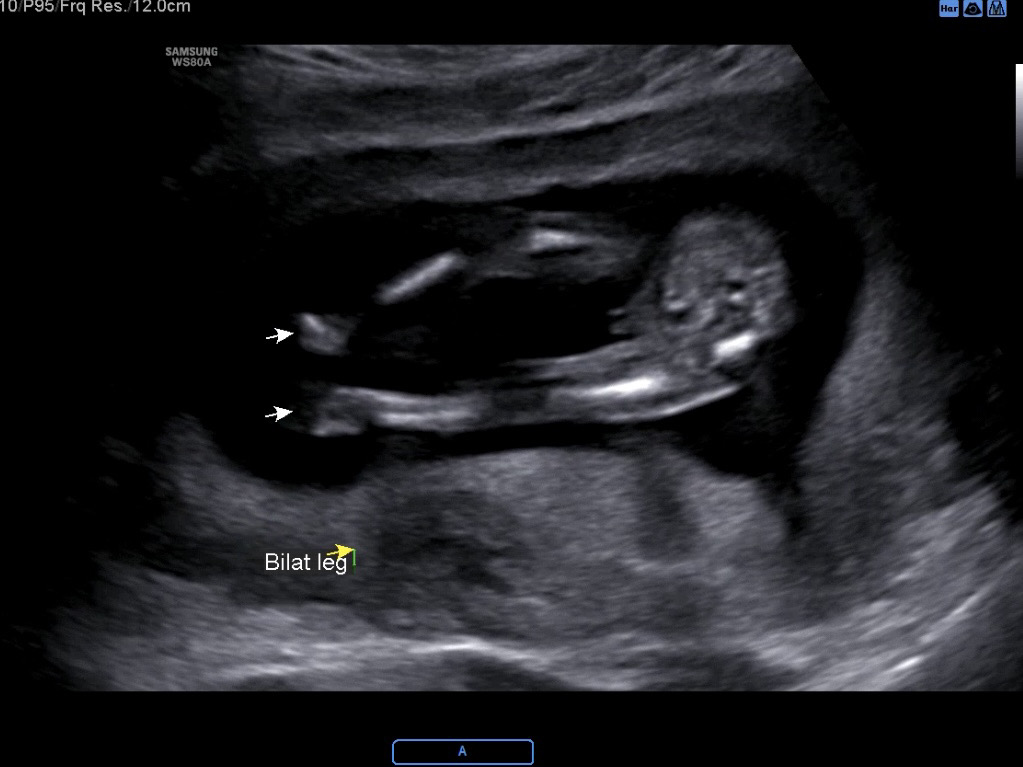

13주차 초음파이구 다리 부분이에요 제 눈엔 🌶️로 보이네요..ㅋㅋㅋ

이 시기엔 딸도 아들도 약간 돌출되어있다고 해요~ 그러다가 딸은 기관이 안으로 들어가 사라지고 아들은 커진대요~